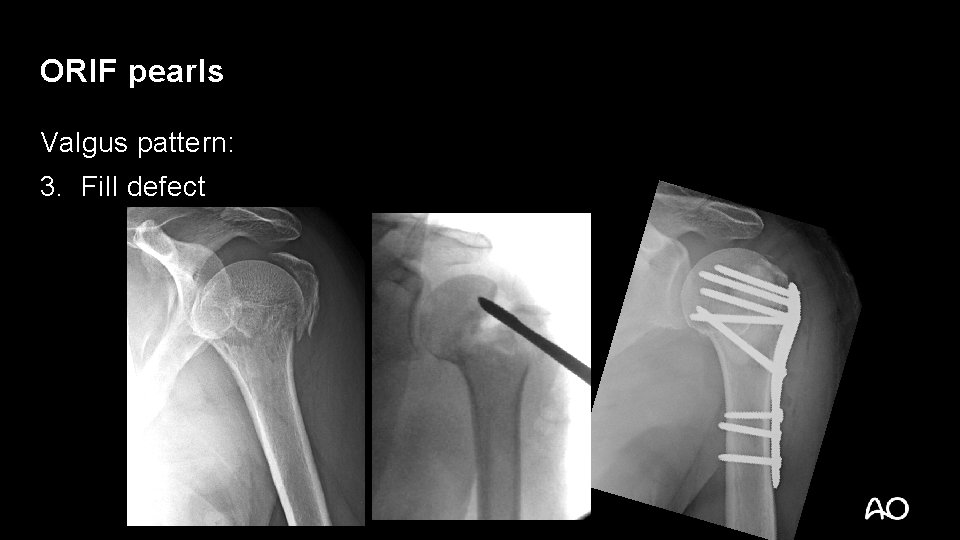

Orif Plate Fixation For 4 Part Slight Displacement Valgus Malalignment